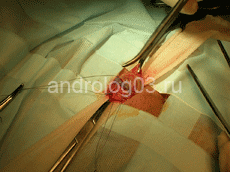

Рисунок 1. Микрохирургическая варикоцелэктомия.

Рисунок 2. Выделенный семенной канатик. Визуализируется варикозно-расширенная вена.

Рисунок 3. Перевязанные варикозно-расширенные вены семенного канатика.

Рисунок 4. Внешний вид после операции.